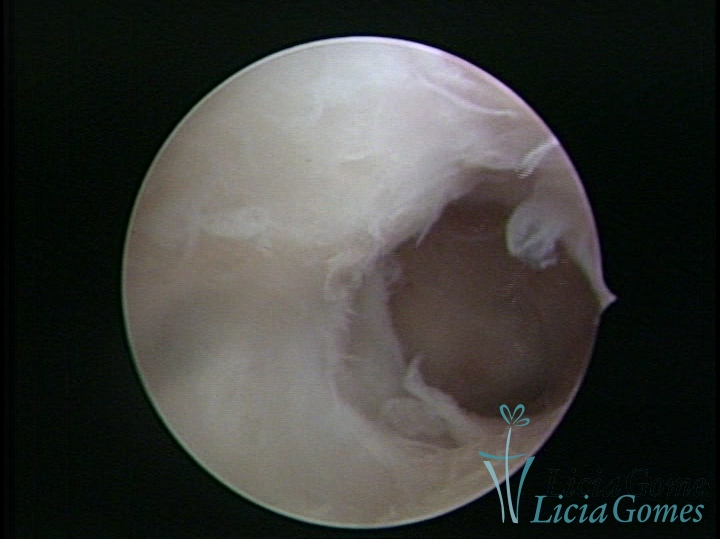

FIBROUS SYNECHIA

Uterine synechiae are scars (adherence) between the surface of the uterine walls, which may occur after the surgical procedure, uterine curettage, or after an inflammatory process in the uterine cavity (endometritis), which may lead to menstrual changes, infertility and obstetric complication such as abortion and premature birth.